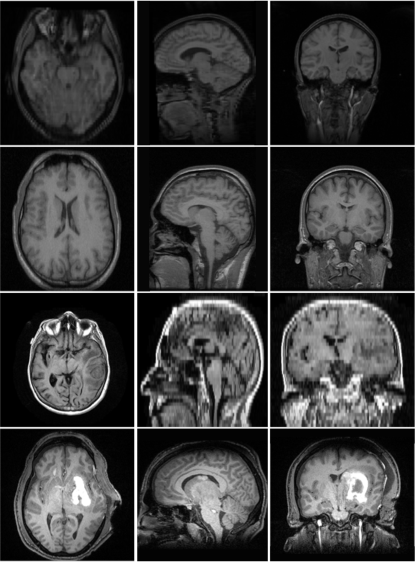

Fig. 1 shows example images from each dataset to illustrate image variability. IBSR and LPBA40 contain images from normal subjects and include large portions of the neck; BRATS has very low out-of-plane resolution; and the TBI dataset contains large pathologies and abnormal skulls.

Refer to caption

Figure 1: Illustration of image appearance variability on a selection of images from each (evaluation) database. From top to bottom: IBSR, LPBA40, BRATS and TBI.